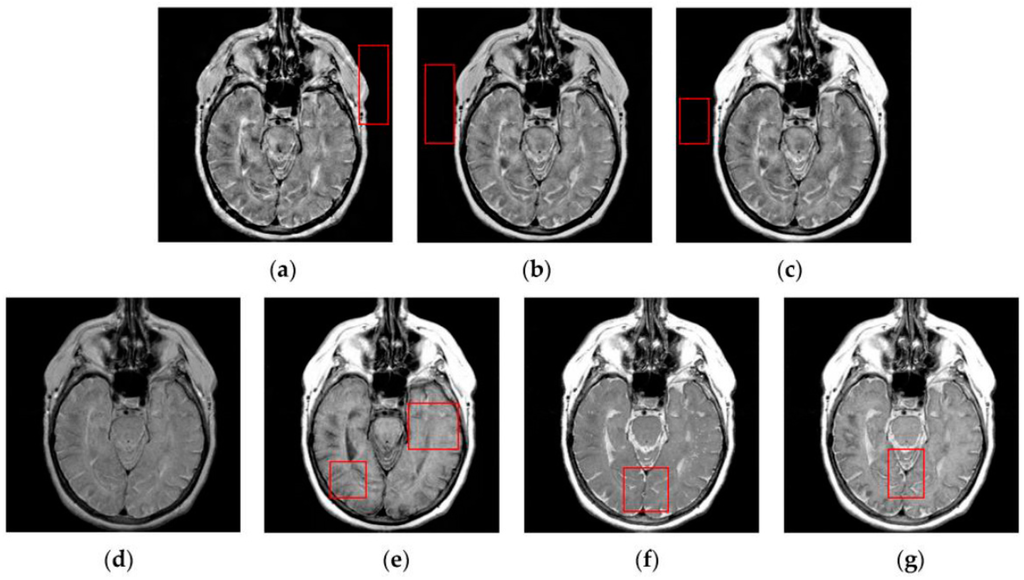

4.2. Visual Comparisons of Fused Results